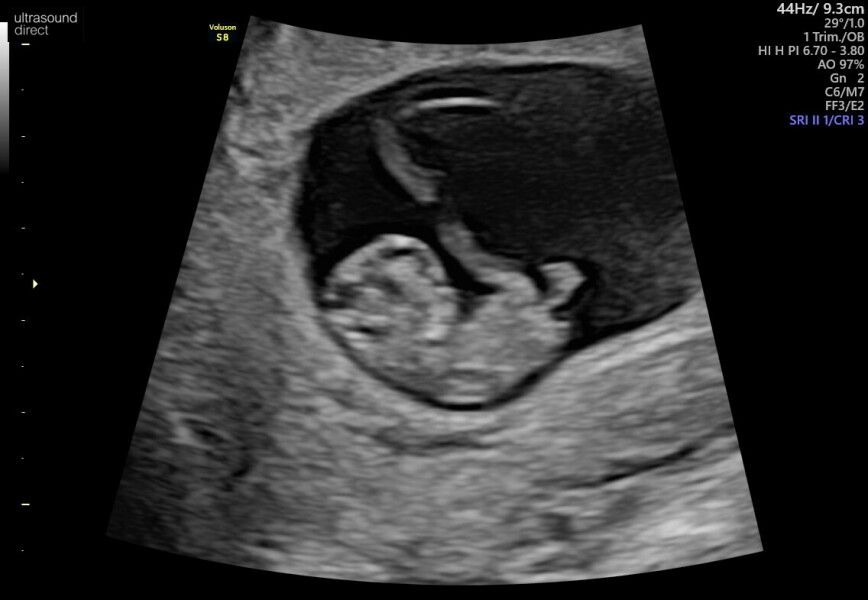

@ToeBeans24 im 10 and half weeks pregnant, had a private scan for peace of mind at 9 weeks and its growing as expected. I think it was what I needed to stop obsessing so much. Just waiting for my nhs scan now and then can finally start telling people

I have zero advice on staying calm I'm afraid 😂 I tested every day for weeks to make sure the lines weren't getting lighter, then I had some bleeding at week 6 and had a complete meltdown and ended up in out of hours so I was not calm at all! Hopefully they book your first midwife appointment in relatively early, mine wasnt until nearly 10 weeks but that made me feel better once I could talk through some of my concerns. And the 9 week scan was a good time, the baby was about 3 cm so you could tell it was a baby and not just a blob on the screen